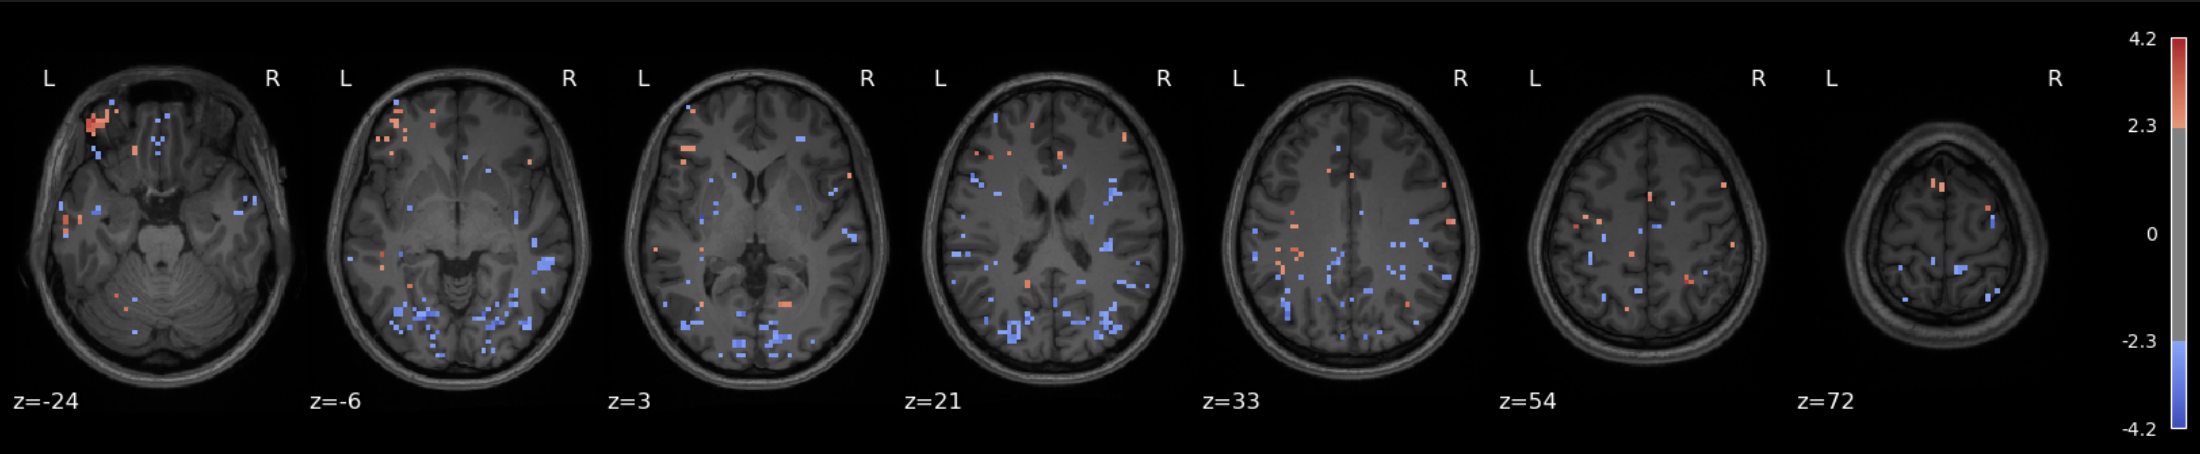

Plot results#

plot_stat_map(

z_map,

bg_img=anat_img,

threshold=1.7, # Tweak this depending on effect strength, here I'm going low to help me 'see' what's going on

display_mode='z',

cut_coords=7,

title='High Fear > Low Fear',

cmap='coolwarm',

vmax=6.0

)

show()

Checkpoint: What do we see?#

Before drawing any conclusions, let’s summarize what was done and what question is being asked.

We fit a first level GLM to some fMRI data for a single run on a single subject who saw animal videos and rated them on how fear-eliciting they were. Our GLM includes one regressor per animal category which was modulated (or weighted) by the fear rating.

The question being asked by this analysis (specifically, it manifests in the contrasts) is: Which voxels show a linear relationship with subjective fear, irrespective of animal category?

And the answer can come in many forms, such as the map shown above, for instance. Note that a low statistical threshold (threshold = 1.7 ≈ p = 0.05ish (one tailed) or p = 0.09ish (two tailed)) was used to ease visualization of what’s happening and where. However, it’s a bit hard to interpret unless you have extensive experience looking at such maps (in addition to the interpretive difficulties associated with single subject/single run analyses in general).

So another step one can take is to use different atlases, which are pre-computed brain maps with specific labels for different regions, and use those maps to figure out which anatomical structures our colorful blobs fall into.